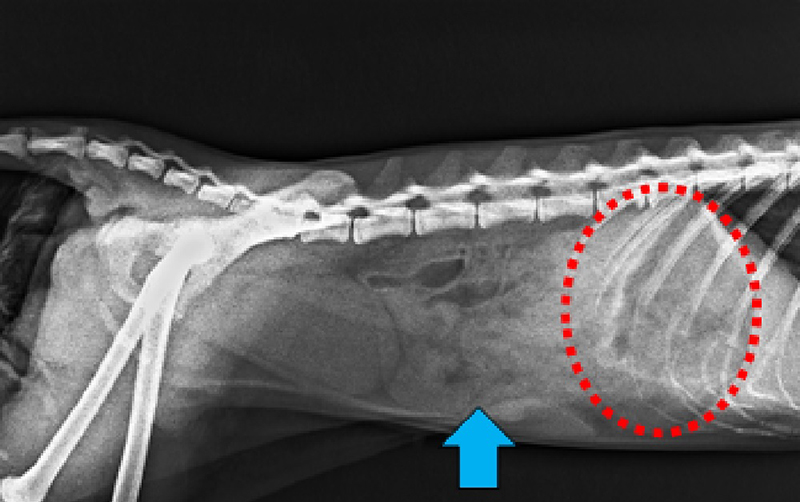

正常な胃と腸管 胃(赤丸)と腸管(青矢印)のなかには食渣が貯留 | 患部写真(術後1週間) 切開部はきれいに癒合している |